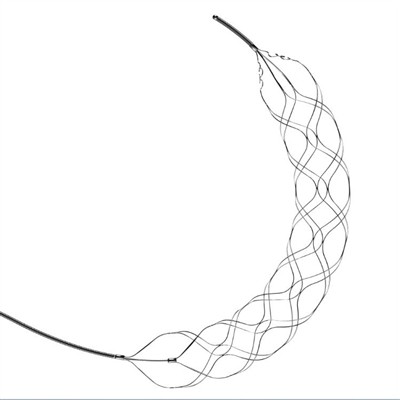

Buntáistí do Thrombectomy Stent RetrieverLe blianta beaga anuas, tháinig aisghabhálaithe stent thrombectomy chun cinn mar rogha cóireála an-éifeachtach d'othair atá ag fulaingt ó stróc géarmhíochaine ischemic. Is éard atá i gceist leis an nó